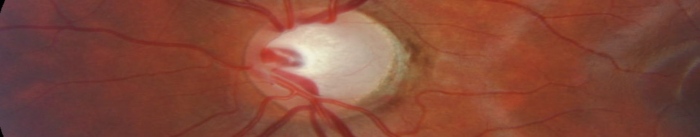

Imagenología y Glaucoma

La imagenología es clave para detectar y monitorear el glaucoma, evitando la pérdida de visión.

OCT: Evalúa fibras nerviosas y detecta daños tempranos.

Fotografía del nervio óptico: Registra cambios en el nervio.

Campo visual: Prueba la visión periférica.

Estas técnicas permiten detectar el daño antes de que aparezcan síntomas, optimizando el tratamiento y preservando la visión.